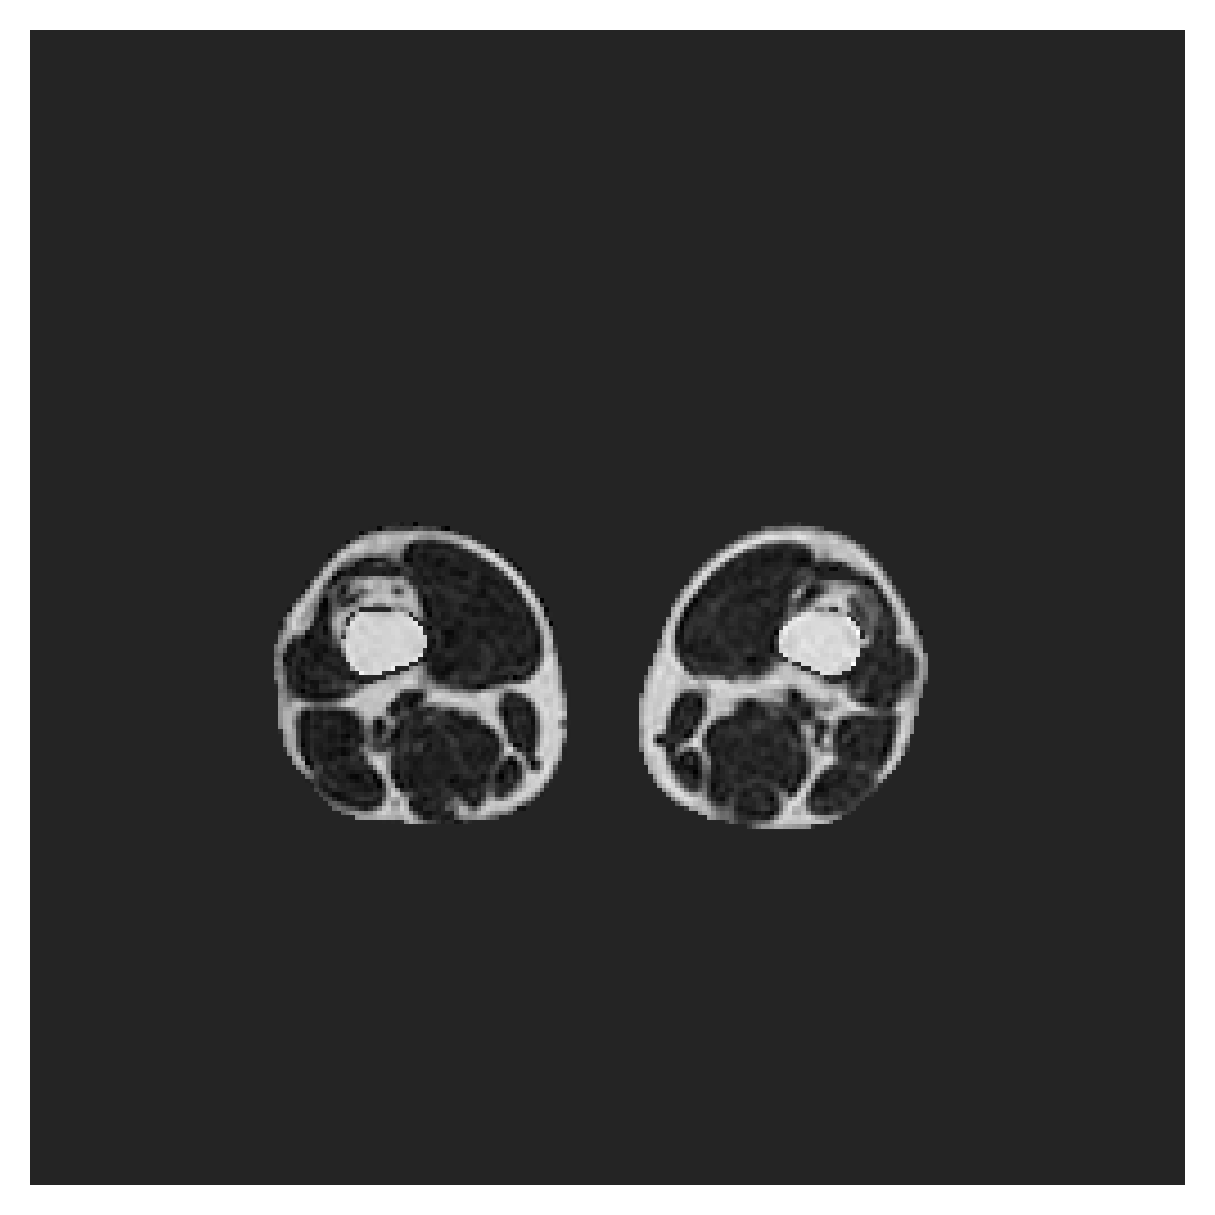

POEM

The Prospective investigation of Obesity, ENergy production and Metabolism (POEM) is a local (not currently publicly available; PI: L. Lind, see [22] for details) cohort of whole-body fat/water separated MR images. Full annotations of the liver, kidneys, bladder, pancreas and spleen are available for 50 subjects, providing a challenging segmentation dataset with heavily imbalanced classes of varying shapes. The resolution of the data is anisotropic, with reconstructed voxel size of in left-right, anterior-posterior and foot-head directions, respectively. For additional technical details regarding the acquisition and specifications of the images see [22].

The images contain two channels, one for water and one for fat content. For training, we normalize the volumes (per channel) and use 2D slices in the coronal plane, sized . The weak annotations are created synthetically, following the same procedure as described for the ACDC dataset.

5.2 Abdominal organ segmentation

Using 2D distance maps

In Table 3, the average DSC and HD95 results are shown (both using 2D and 3D distance maps) for the task of abdominal organ segmentation in POEM data (for boxplots see figures 8 and 9). We see that training with and (with distances calculated on 2D slices) performs comparably, while using and produces lower scores in both DSC and HD95 metric. On this dataset, the CRF-loss is able to compete with the boundary loss-based training strategies, even outperforming them on most classes. Most notably, all models trained with boundary loss appear to have a hard time segmenting the liver. We hypothesize this may be due to extremely severe class imbalance, as the liver covers a very large area compared to the rest of the classes. It is thus also more strongly affected by undersegmentations.

5.2.1 Qualitative comparison

In Figure 11 and 12 we show the same random slices in cases of calculating the boundary loss on 2D- and 3D-based distances, respectively. Comparing the two figures again indicates that the intensity-aware distances offer most improvement when calculated in 3D over 2D. The exception here is the MBD, which seems to even slightly degrade for most classes.